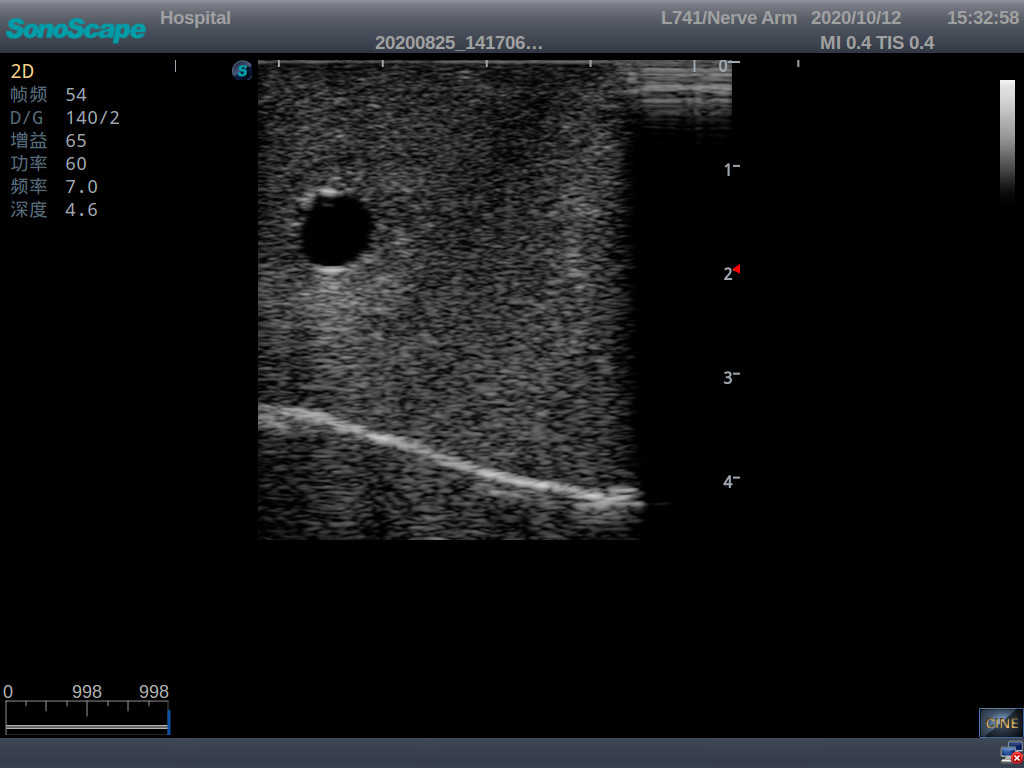

2)  The puncture module supports using a clinical real ultrasound machine to observe clear images such as right internal jugular vein, right common carotid artery, superior vena cava, right brachiocephalic vein, right brachiocephalic trunk, right subclavian vein, right subclavian artery, etc.

3)  The puncture pad at the arm is made of high-molecular ultrasound material, close to real skin. It can support the use of real ultrasound machines, and the images of tissue structures (skin, subcutaneous tissue, blood vessels) under ultrasound are clear and real